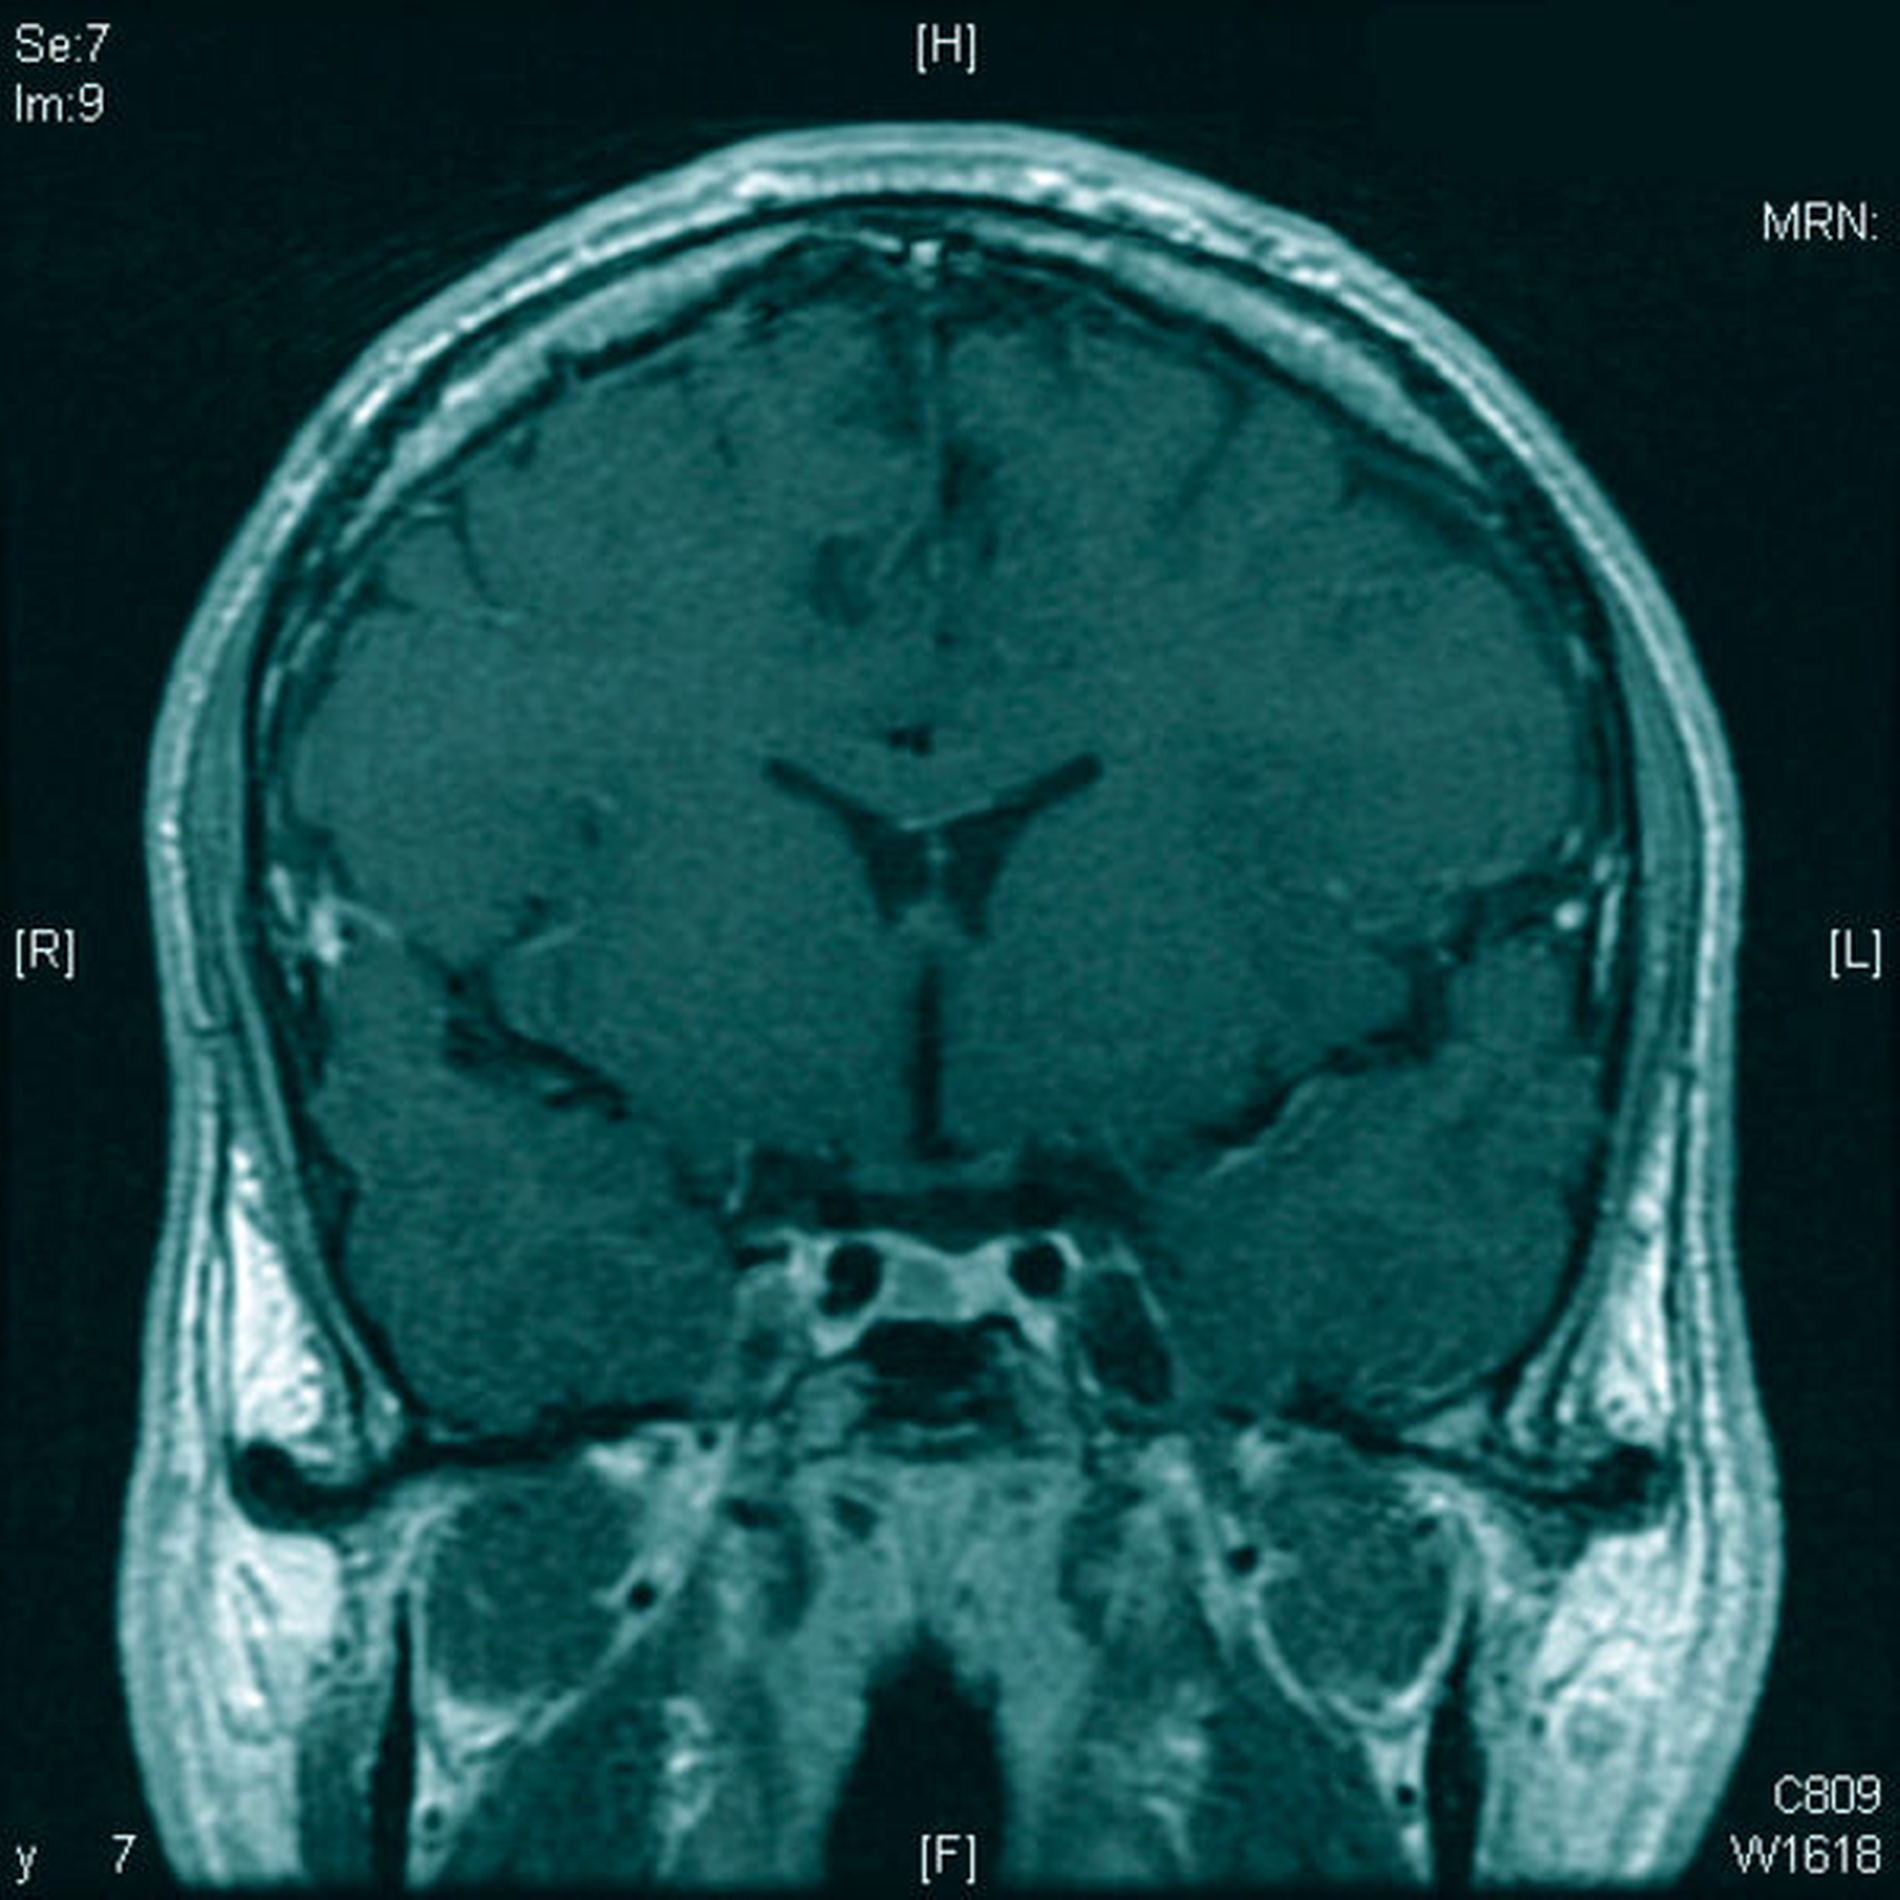

Aufgrund erhöhter Spiegel von STH und IGF-1 sowie eines in der MRT erkennbaren intrasellären Hypophysenadenoms (Abbildung 3) erfolgte im November 2015 eine endoskopische transsphenoidale Resektion des Hypophysenadenoms durch die Kollegen der Neurochirurgie.